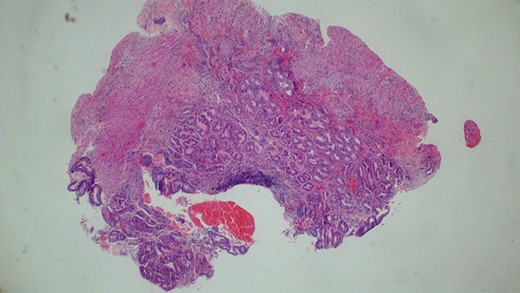

The baby was prepared and taken for an emergency laparotomy whereby intraoperatively, a gastric perforation was found measuring 0.5 by 0.5 cm, circumferential and located on the anterior aspect of the stomach body near the pylorus (Fig. 2). There was also about 50 ml of amber-colored ascites. The perforation was repaired and Grahm’s patch was put, thorough abdominal lavage and the abdomen was closed in layers. Biopsy from the perforation site revealed non-necrotizing mild chronic gastritis, not otherwise specified with ulcerations (Figs 3 and 4).

Histopathology of the biopsy from the gastric perforation showing near full thickness with non-specific mixed chronic inflammation (H&E staining, x10).